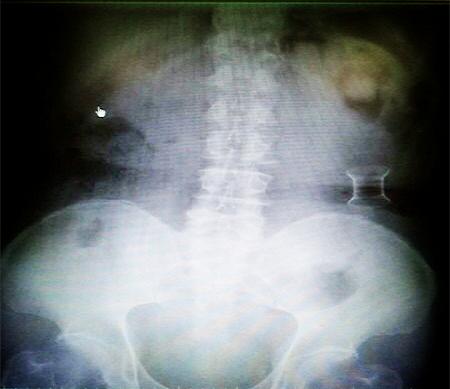

受試患者在結(jié)腸端端吻合術(shù)中,使用我司新研制產(chǎn)品達到了理想的預(yù)期效果?;颊咝g(shù)后7天、14天X光片顯影,可降解腸道支架均能按研制設(shè)計的預(yù)期時間節(jié)點保持應(yīng)有強度,術(shù)后21天X光片顯示可降解腸道支架已完全破碎,并排出體外。在整個試驗過程中,病患無任何不良反映,耐受良好。